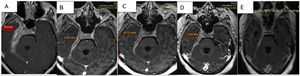

Un mes posterior al inicio del tratamiento se realiza RMN de control donde se evidencia la disminución del compromiso de estructuras vasculonerviosas alrededor del seno cavernoso, quiasma óptico, disminución del edema del parénquima cerebral y disminución del espesor y el realce meníngeo en la base del cráneo.

Discusión de las imágenesEn los estudios sucesivos de resonancia magnética se evidencia tejido patológico que engrosa las meninges con un espesor de 19,5mm, y que muestra señal isointensa en T1, hipointensa en T2 y tiñe con el contraste con moderada restricción a la difusión del agua.

Compromete la base de cráneo en topografía parasagital derecha, con extensión hacia el conducto carotídeo, foramen yugular, agujero rasgado posterior, peñasco y tienda del cerebelo homolateral. Invade. Además. el conducto auditivo interno, el seno cavernoso y el vértice de la órbita derecha, con compromiso paquimeníngeo a nivel de la fosa temporal profunda rodeando circunferencialmente los pares craneales III, V, VI, segmento cisternal e intracavernoso, VII y VIII a nivel del conducto auditivo interno.

Se observa progresión de la paquimeningitis con compromiso de la región anterior del quiasma óptico, el cual se observa engrosado con refuerzo poscontraste. Reemplaza a la vena yugular interna derecha en su foramen, no evidenciándose opacificación del segmento proximal de la misma. Defecto de relleno parcial del seno sigmoideo homolateral.

Comparativamente se observa respuesta parcial al tratamiento instaurado con relación al estudio de base con espesor paquimeníngeo de 19,5mm al inicio; en los controles presenta disminución de 10,5mm (53% del tamaño inicial) a la semana del pulso de corticoides; a 8,7mm (44% del inicial) con corticoides más rituximab; y en el último control, luego de 3 meses del inicio del tratamiento, con corticoterapia de mantenimiento 10mg/día de prednisona y metotrexato presenta 7,8mm (40% del tamaño inicial) (figs. 3A-D).

Secuencias en T1 de la RMN sucesivas en la evolución de la paciente. Desde (A) lesión basal con engrosamiento de aproximadamente 2cm, hasta (D) estado posterior al tratamiento con esteroides y rituximab que evidencia la mejoría franca del engrosamiento y el edema. E) Cortes tardíos que muestran zonas de fibrosis.

En el último control se observa disminución del engrosamiento paquimeníngeo descrito en los estudios anteriores, a nivel del quiasma, del conducto auditivo interno, del seno cavernoso, y espesor de fosa temporal; y al realizarse cortes tardíos a los 30min se identifica mayor realce del tejido paquimeníngeo en relación a componente fibrótico (fig. 3E).